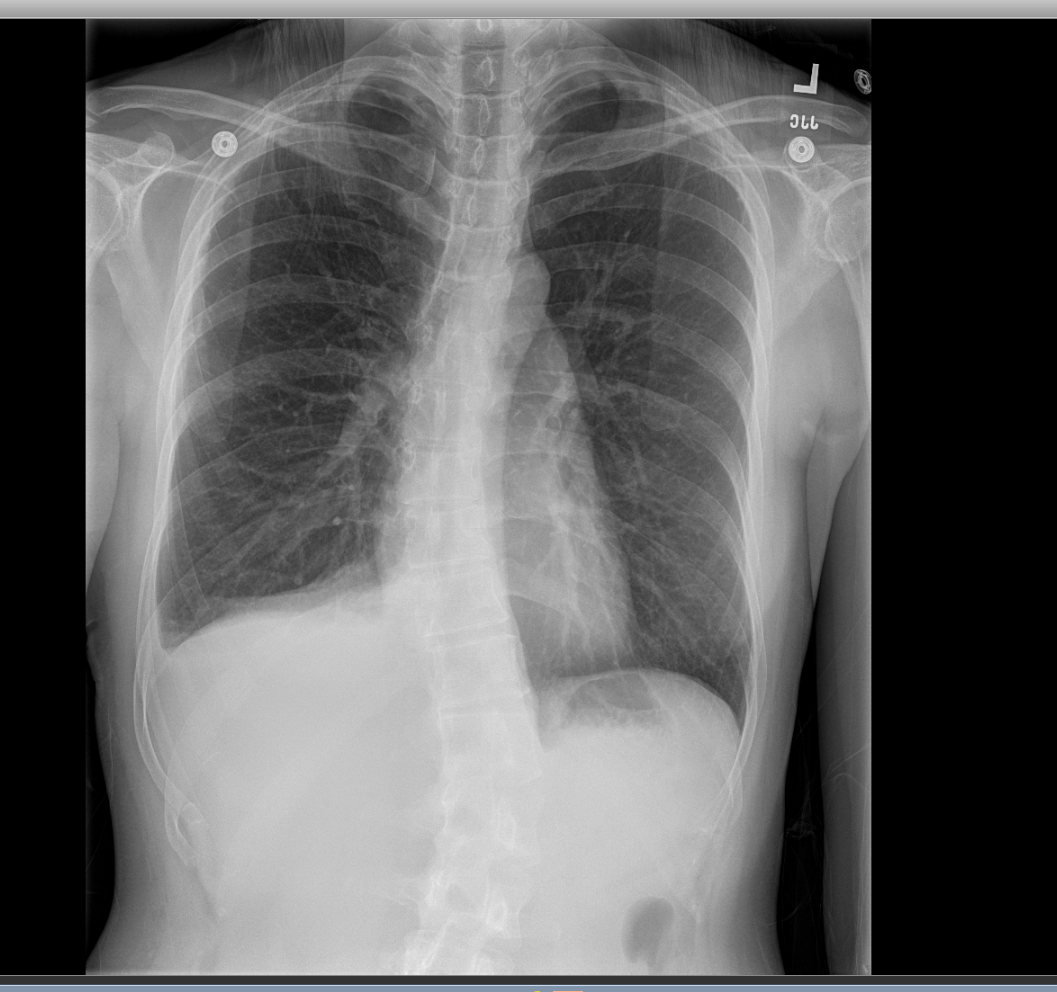

Case Presentation: A 37-year-old Korean female presented with 3-day history of worsening right posterior shoulder and chest pain, and exertional dyspnea. Review of System was otherwise negative. Past Medical History included chronic hepatitis B and an episode of pneumothorax 1 month prior. Her LMP was 2 weeks prior to presentation. On exam, she was tachypneic with absent breath sounds in the upper right lung zones. Vitals were otherwise within normal limit. Chest X-ray revealed moderate to large right pneumothorax (Fig 1). Labs were unremarkable including a normal α-1 antitrypsin assay. A chest tube was placed. On day 2 of admission the patient had video-assisted thoracoscopic surgery (VATS) with mechanical pleurodesis. Multiple diaphragmatic defects with endometrial deposits were found. The chest tube remained in situ for the duration of the hospital stay and removed 24 hours prior to discharge (Fig 2). Pelvic ultrasound was unremarkable and she was started on oral contraceptive pills.